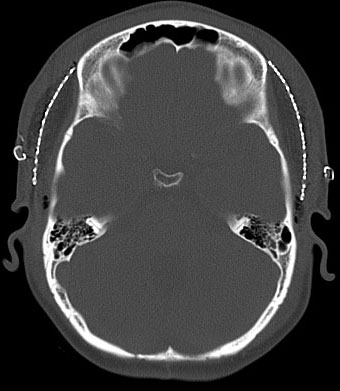

20年以上前のことですが,髄芽腫の1歳6ヶ月の子どもに25グレイの全脳照射をしました。これは15年後のCTです。

脳の萎縮は目立ちません。認知機能は低いのですが支援を受けて学校へ行けています。下垂体機能は低下して成長ホルモンなどの補充をして普通に暮らせています。

CTで,両側の大脳基底核(被殻と淡蒼球)と視床後部に石灰化がみられます。乳幼児期に放射線治療を受けた子どもに見られるものです。